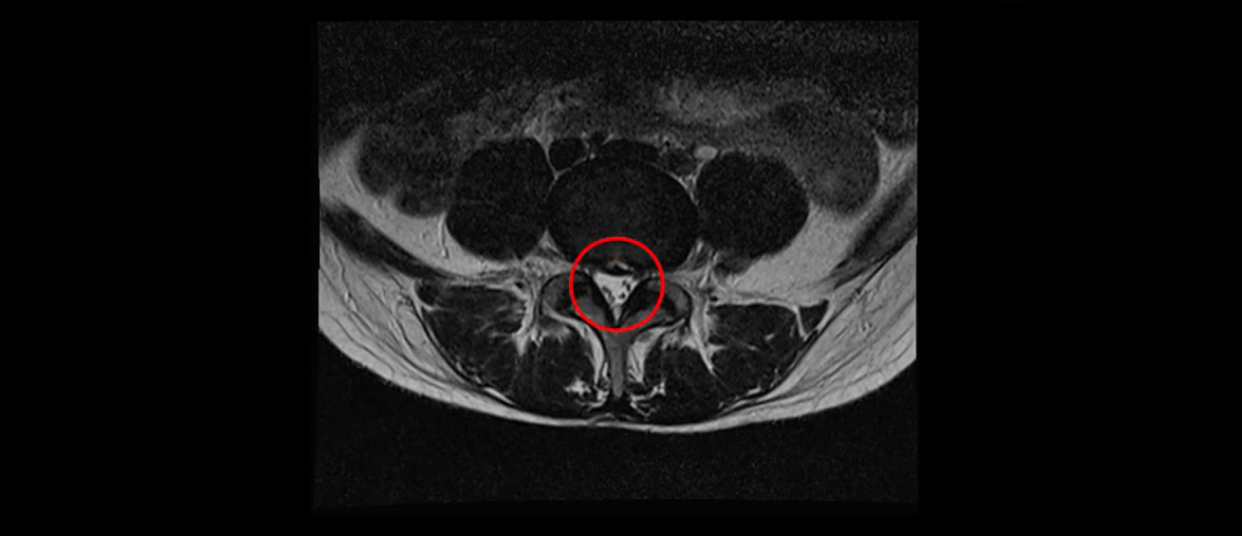

이분 MRI를 보시면 두 마디의 퇴행성디스크가 있습니다. 그리고 디스크가 조금씩 밀려 나와 있고요. 그런데 디스크 탈출 정도는 두 마디 다 심하지 않습니다. 4번 5번에는 디스크 탈출이 약간 있고,

5번 1번은 디스크 탈출이 가운데 쪽으로 살짝 있습니다.

또한 양쪽 신경 가지가 빠져나가는 추간공은 매우 넓은 상태입니다.

중요한 것은 이 정도 경미한 탈출과 협착으로는 양쪽 다리가 저리고 아플 수가 없습니다.

이분 MRI를 보시면 퇴행성디스크가 있고 약간의 협착이 있지만 이 정도의 퇴행성디스크와 협착으로는 신경이 눌려서 양쪽 다리가 저리고 아픈 증상이 나올 수가 없습니다. 그래서 MRI와 이 환자분의 다리 증상이 매치가 안 된다고 하는 의사들이 많은 겁니다.